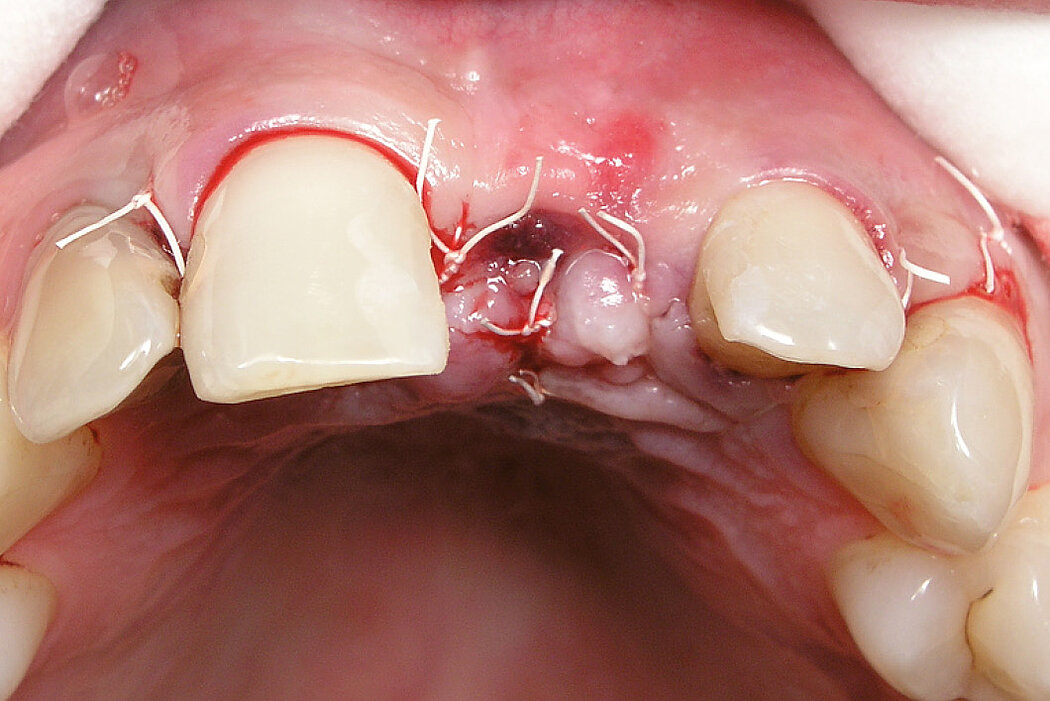

颊侧骨壁完整时的牙槽窝内牙槽嵴保存

病例来自 Dr. Hadi Antoun & Dr. Bouchra Sojod

法国,巴黎

临床挑战

使用选定的生物材料,保存前牙区的硬组织和软组织,以便进行延迟种植。

目的/方法

拔牙后的硬组织和软组织保存。延迟种植是一种非常可靠的手术,国际文献中已反复证实了这一点。

结论

Geistlich Bio-Oss® Collagen 和 Geistlich Mucograft® Seal 在术后5个月可实现牙槽嵴保存,为种植体固定提供最佳条件。在中切牙处,使用结缔组织移植物优化颊侧软组织厚度。